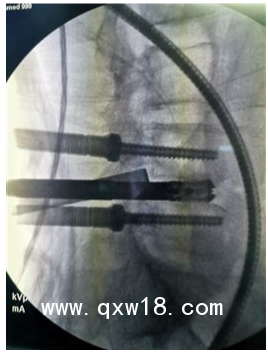

UBE(unilateral biportal endoscopy)技術(shù)是指單邊雙通道內(nèi)鏡下的脊柱手術(shù),是一項(xiàng)新興的微創(chuàng)技術(shù), UBE在脊柱疾病的治療中療效確切,值得進(jìn)一步研究與應(yīng)

UBE的技術(shù)特點(diǎn):

1.兼有內(nèi)鏡放大的視野和開放手術(shù)靈活的操作;

2.應(yīng)用常規(guī)椎間孔鏡器械和脊柱開放手術(shù)器械;

3.對(duì)肌肉損傷較小、透視少(可能為零);

4.可以進(jìn)行鏡下融合;

5.對(duì)椎管狹窄具有獨(dú)特的優(yōu)勢(shì);

6.有內(nèi)鏡操作經(jīng)驗(yàn)者學(xué)習(xí)曲線較短;

7.條件成熟同樣可以用于頸胸段。

目前UBE手術(shù)適應(yīng)證主要包括:

1.各種類型的腰椎間盤突出癥(側(cè)隱窩);

2.椎管狹窄癥;

3.輕度的腰椎滑脫(BE-TLIF);

4.腰椎不穩(wěn)伴或不伴上述疾病。

UBE技術(shù)較常規(guī)單通道內(nèi)鏡技術(shù)相比,具有其獨(dú)特的優(yōu)點(diǎn):

1.使用關(guān)節(jié)鏡器械及傳統(tǒng)脊柱開放性器械進(jìn)行操作,無需購置特殊孔鏡設(shè)備及器械,高效利用,節(jié)約成本;

2.雙通道設(shè)計(jì),關(guān)節(jié)鏡的獨(dú)特放大功能,手術(shù)視野寬闊清晰,操作通道具有開放性手術(shù)靈活性;

3.使用常規(guī)開放手術(shù)器械進(jìn)行操作,效率更高;

4.對(duì)肌肉損傷較小,透視次數(shù)極少(1次即可),減少醫(yī)患X線暴露的風(fēng)險(xiǎn);

5.對(duì)椎管狹窄的同側(cè)減壓及對(duì)側(cè)減壓具有其獨(dú)特的優(yōu)勢(shì),同時(shí)也可行鏡下融合;

6.同樣適用于一些高齡、需要減壓融合或者翻修等特殊病例的微創(chuàng)處理